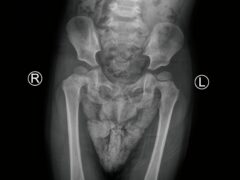

Pediatric pelvis X-ray radiograph showing bilateral hip dysplasia, developmental hip abnormality, femoral heads, acetabulum, and pelvic bones. Medical diagnostic imaging for congenital hip disorder.

Problemas de cadera en lactantes

¿Cuáles son los problemas de cadera en bebés? El problema de cadera en los bebés se conoce como displasia del desarrollo de la cadera (DDH). Es cuando la bola de la articulación de la cadera no est...